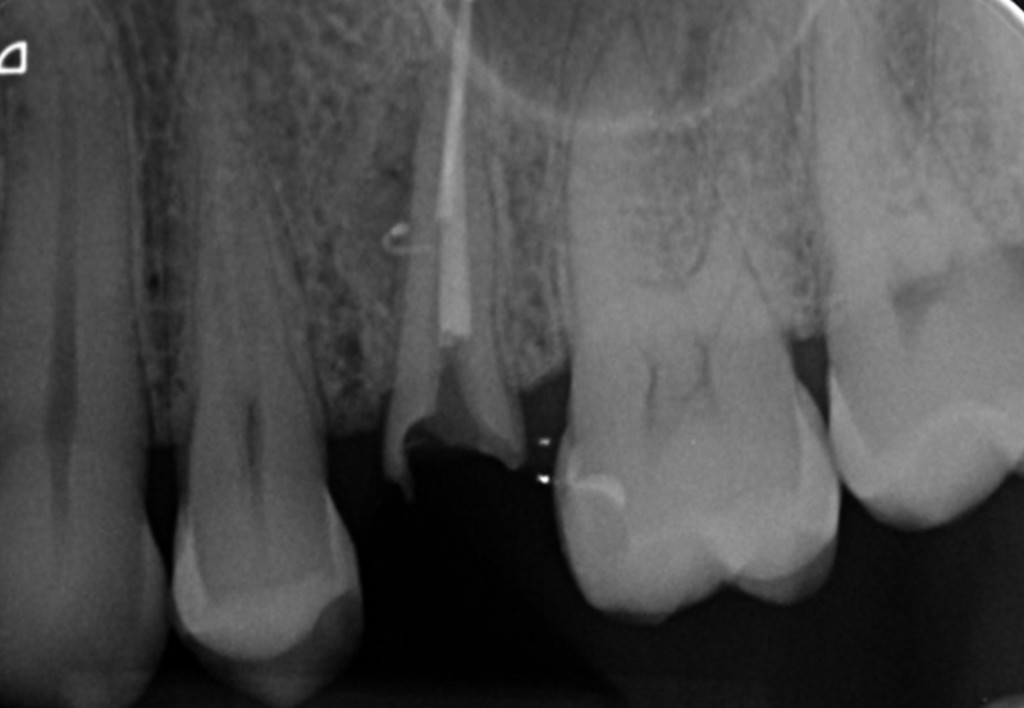

Galleria fotografica